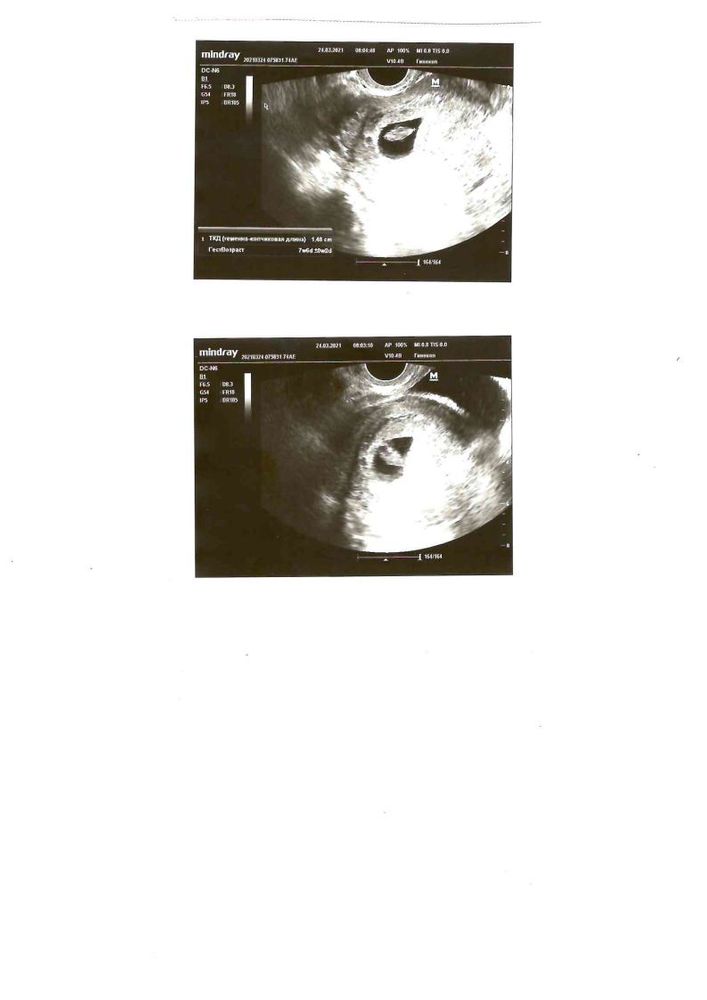

Стало интересно, у кого совпадало?Суть метода в том, что на сроке 6-8 недель по узи можно определить мальчик или девочка по прикреплению хориона и эмбриончика естественно.

Я по своему узи совсем не пойму..может кто подскажет?